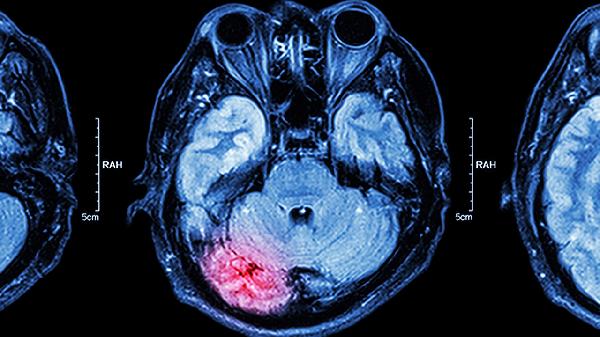

该药可扩张脑血管,增加脑血流量,缓解因高血压导致的脑供血不足。典型表现为头重脚轻、视物模糊,严重时可伴耳鸣。需注意脑出血急性期禁用。同类改善脑循环的中成药还有养血清脑颗粒、松龄血脉康胶囊等。